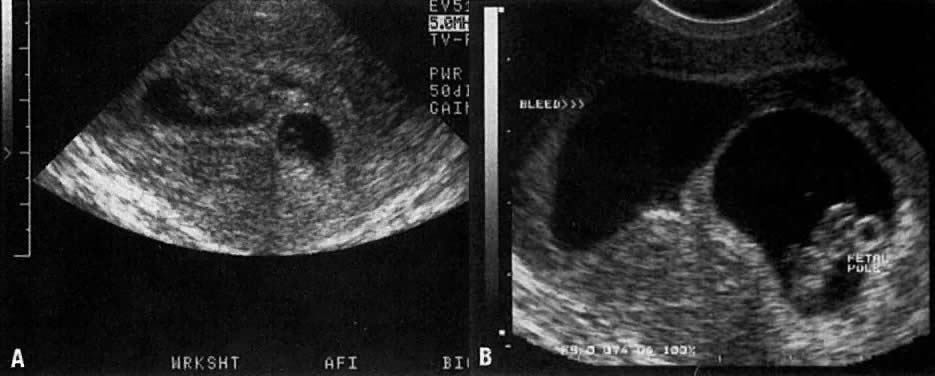

Approximately 15% to 20% of women have a spontaneous, clinically recognized pregnancy loss in the first trimester.5 Ball and co-workers6 found that a subchorionic bleed (identified on ultrasound) is associated with an increased risk of miscarriage, stillbirth, abruptio placentae, and preterm labor (Fig. 4A and Fig. 4B). Their data suggested that the risk of spontaneous abortion increased in proportion to an increase in the size of the subchorionic bleeds; however, a larger sample size was needed to determine statistical significance. Bradycardic fetal heart rates, small sac size, abnormal yolk sacs (Fig. 5), and large subchorionic bleeds have all been associated with an increased risk of first-trimester pregnancy loss.7

Fig. 4A. A 7-week intrauterine gestational sac with a large subchorionic bleed and clot. B. Ten days later, the clot has resolved but a residual subchorionic bleed is noted.